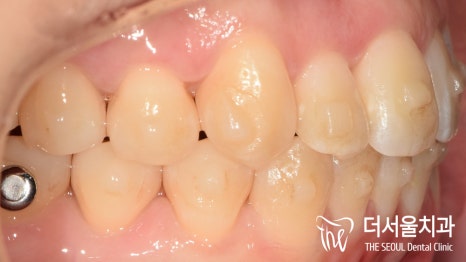

심미성이 기준이 되는 미드라인이

일치되었습니다.

교합면에서 봤을 때에, 치열이

알파벳 U 자 처럼 보여지죠?

윗니와 아랫니가 잘 맞물리게끔 재 배열을 했습니다.

즉, 기능성도 같이 향상 되었다는 뜻입니다.

측면에서 바라봤을 때에도, 전과는 다르게

뻐드러짐이 없어진 것이 확인 됩니다.

총 1년 9개월의 기간이 걸렸습니다.